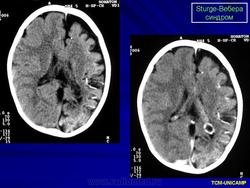

Компьютерная томография пациента с болезнью Штурге - Вебера